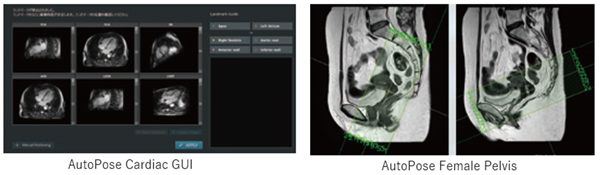

スライスライン設定サポート機能AutoPose※2

AutoPoseは全身幅広く進化した対象部位

VINCENT※3 で蓄積した豊富なCTのデータをAI技術でMRI画像に変換する技術を確立しました。この技術と臓器セグメンテーション開発で構築したCNNライブラリをMRI位置決め開発に活用し,多くの部位で精度の高い位置決め機能※4 を製品化しました。